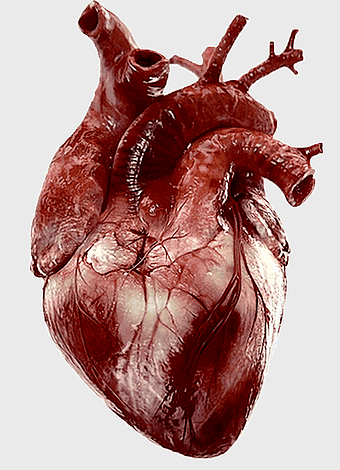

human heart anatomy, cardiovascular system illustration, medical heart diagram, heart organ structure, human body organ visuals, anatomical heart drawing, heart health -

human heart anatomy, superior vena cava illustration, systemic circulation diagram, heart rate visual, cardiovascular system study, medical organ depiction, human body organ reference -

Heart Anatomy Diagram, human heart drawing, realistic heart illustration, cardiovascular system, medical illustration, organ structure, human anatomy study -

human heart anatomy, cardiac muscle illustration, circulatory system model, heart health visual, cardiovascular organ diagram, medical heart image, visceral structure depiction -